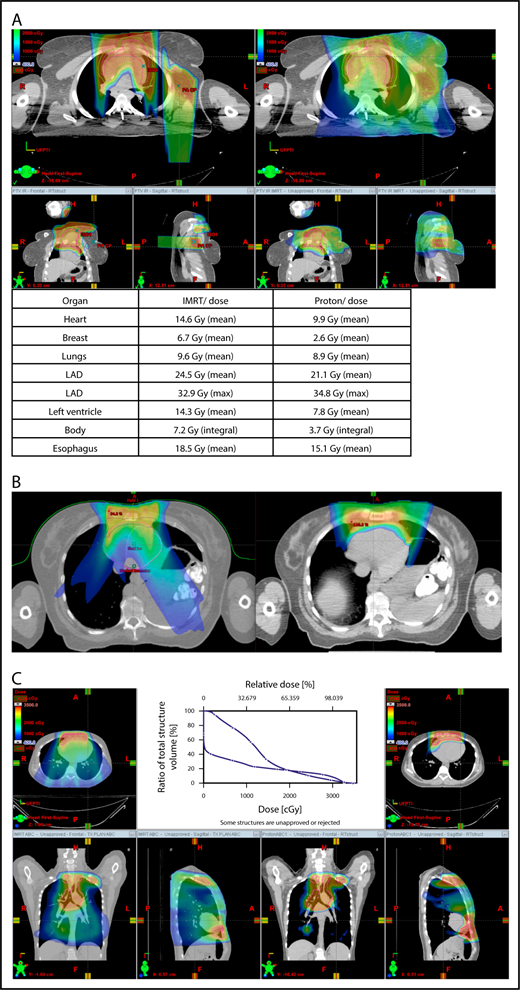

Axillary involvement at presentation. (A) Axial, coronal, and sagittal views of a proton plan (left) and an IMRT plan (right) for a patient presenting with axillary involvement. Use of proton therapy in this case spares the left breast. (B) Regardless of which treatment modality is chosen, IMRT (left panel) and proton (right panel), limiting the volume exposed to radiation should include attention to avoiding a low-dose bath. (C) Limiting lung dose. If avoiding the lung is the primary objective in a given patient, especially if the patient has received pulmonary toxic chemotherapy (eg, any combination of bleomycin, busulfan, gemcitabine, brentuximab, etc.), proton therapy may better spare the lungs by reducing the low-dose bath seen with photons.

Proton therapy can significantly reduce the radiation dose to the breasts by specifically using fields that enter posteriorly and stop short of exiting through the breast. Alternatively, if protons cannot be used, other methods of displacing the breast can be used instead, such as using an inclined board or physically moving the breast out the beam path. Figure 3A shows how using proton therapy can spare the breast in a case with axillary involvement.

Consideration of breast dose

The long-term risk for developing breast cancer is related to exposure to high and low radiation doses.37,52 Especially when treating young patients, efforts must be directed to keeping the radiation dose to the breast tissue as low as possible. In most cases involving mediastinal disease, the axilla is uninvolved, and the radiation dose to the breast with IMRT or proton therapy will be small. Although IMRT leads to greater volumes of breast tissue receiving low-dose radiation, in some cases proton therapy can lead to greater volumes of breast tissue receiving high-dose radiation. It is unknown whether it is more important to minimize the low-dose portion vs the high-dose portion; subsequently, mean breast dose continues to be the best factor for evaluating different plans. However, at this time, a high dose to a small volume is generally favored over a low dose to a large volume based on findings suggesting that doses as low 4 Gy37 can be associated with a risk for long-term second malignancies, especially in patients younger than 24 years of age. Although the dose calculation by Travis et al37 refers to a point dose (not a mean), we still recommend erring on the side of caution in an attempt to keep the mean breast dose ≤ 4 Gy.

When hilar disease needs to be covered, the dose to the breasts can increase, and avoiding the breasts becomes difficult with either modality (proton or photon). The choice of treatment modality for such cases must consider the doses received by other critical structures, such as the heart and lungs, especially in previously and heavily treated patients. However, in considering how to best limit the volumes exposed to radiation, avoiding “low-dose baths” is equally important (ie, irradiation of large volumes with low doses), regardless of which modality is used (Figure 3B).

Consideration of lung dose

With the advent of CT-based planning for mediastinal lymphoma, the dose to the lungs can now be correlated with the risk for pneumonitis. Restrictions on lung dose are encouraged to be V5 < 55%, mean lung dose < 13.5 Gy, and V30 < 20%. These values are more attainable with the use of DIBH.38 Although a mean lung dose of 13.5 Gy has been associated with a lower risk for pneumonitis, it is advisable to aim for a lower dose, which is quite often attainable when strict constraints are used. For example, when IMRT is used, it is important to limit the beams to some variation of anteroposterior beams, avoiding lateral beams. If avoiding the lung is the primary objective for a given patient, especially if that patient has received pulmonary-toxic chemotherapy (eg, bleomycin, busulfan, gemcitabine, brentuximab), proton therapy may better spare the lungs by reducing the low-dose bath seen with photons (Figure 3C).